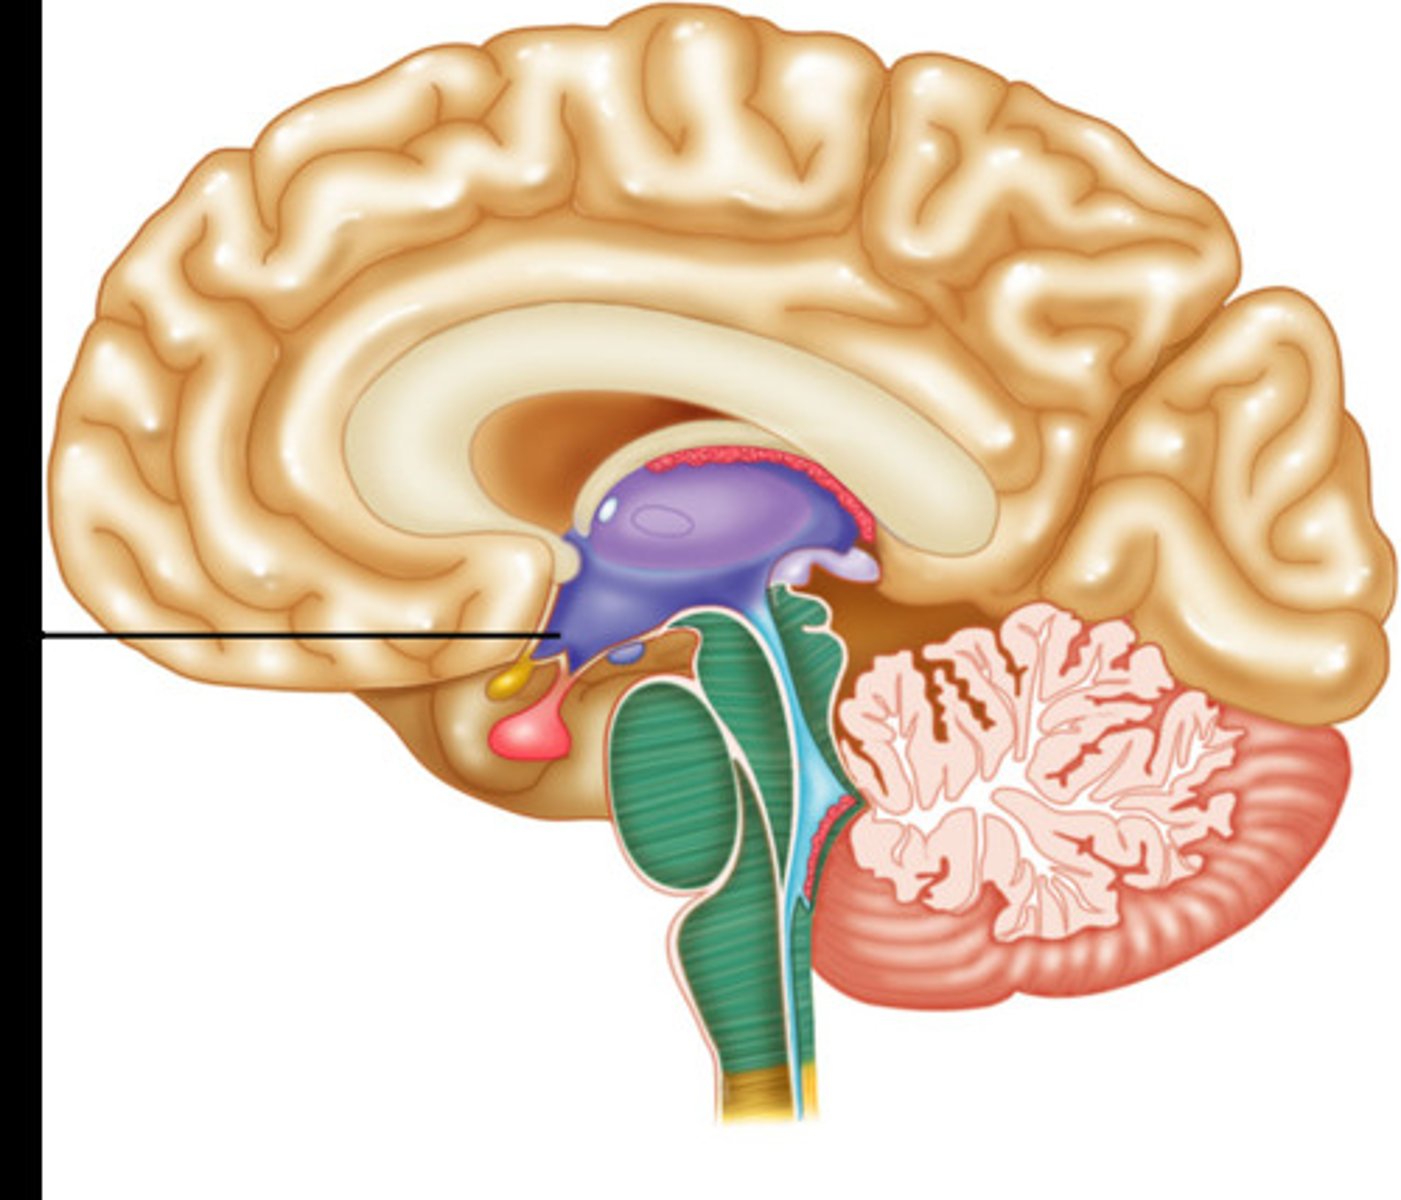

Hypothalmus

Part of the limbic system. Helps body to maintain balance and homeostasis. Controls drives such as thirst and hunger. Ex: Triggering the feeling of hunger when your blood sugar drops.

Pituitary gland

Regulates hormones which release glands to regulate bodily function. Ex: Releasing growth hormones into the bloodstream during puberty.